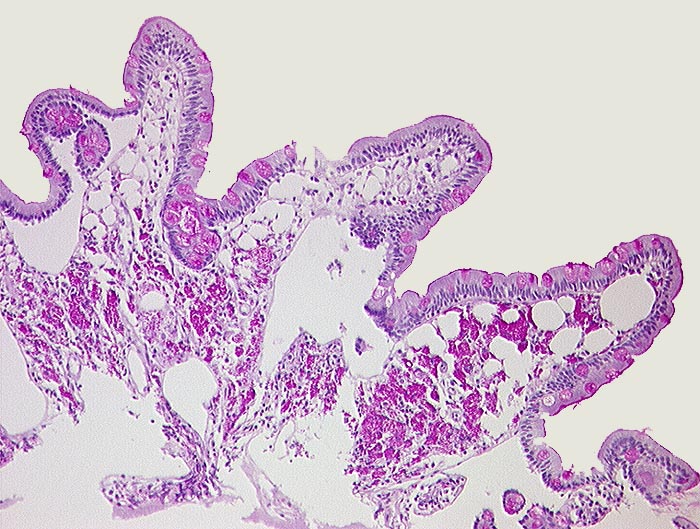

PathoPic ID 433 - Morbus Whipple

Morbus Whipple

Entzündung infektiös

Dünndarm

Darm, Anus

Ektatische Lymphgefässe in den Dünndarmzotten und massenhaft PAS positive Makrophagen im Stroma.

Histologie